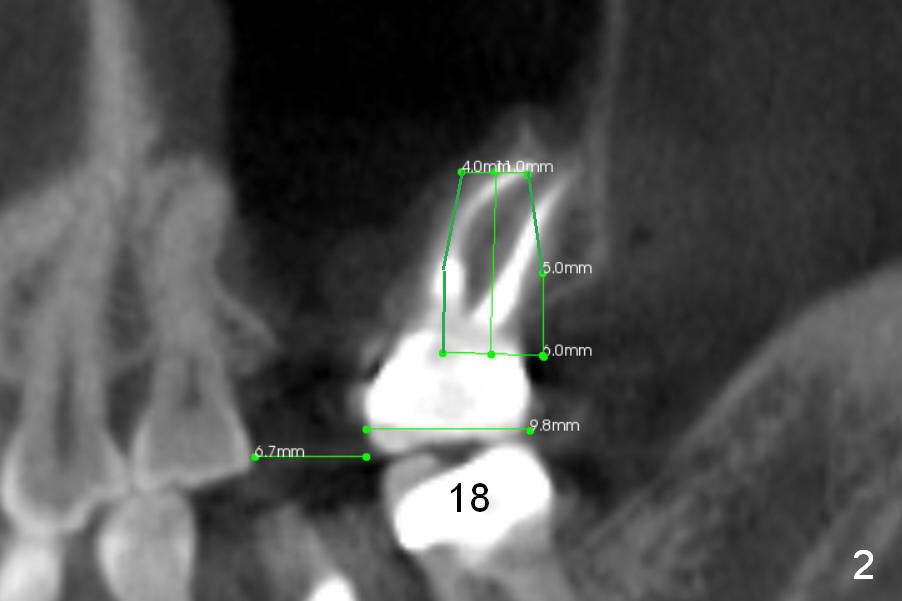

After immediate implant at the site of #19, pain is getting worse at #15 (Fig.1 CT sagittal section). The patient requests extraction, although the etiology of the pain remains unknown. The tooth #14 has been missing 13 years. The tooth #15 has tilted mesially. If an immediate implant is placed along the long axis of the tooth, it is 14 mm long (Fig.1). When the axis is changed according to the opposing dentition (Fig.2), the implant could be 3 mm shorter.